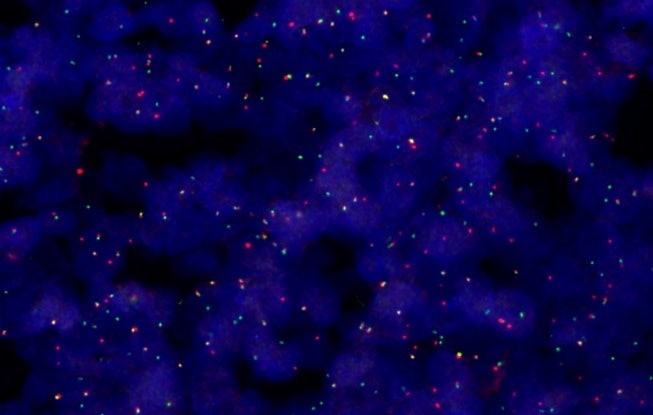

FISH 분석, 40X

명시야, 편광, 형광, 암시야, 위상차의 다섯 가지 이미징 모드를 사용하고 여러 기법을 단일 스캔에 조합하여 샘플에서 더 많은 세부 정보를 발견하세요. 이러한 유연성은 일상적 병리학부터 암 조직의 복잡한 세포 특성 분석까지 조직학 및 세포학 샘플을 관찰할 때 다양한 가능성을 열어 줍니다.